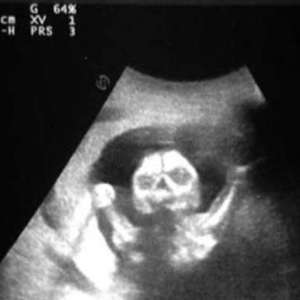

9 лет работаю узистом в детской больнице. Думал, аппаратура не умеет врать… пока ребенок в животе 10-летней девочки не исчез у меня на глазах.

Смены у нас быстрые: поток пациентов, УЗИ, отчёты. Вчерашний вечер тянулся — три плановых, один вне очереди: девочка 10 лет, жалобы на острую боль в животе из-за ... беременности.

Она пришла одна. По-хорошему, я должен был вызвать полицию и ее родителей, но девочка умоляла осмотреть ее в срочном порядке из-за невыносимой боли. Первые пару секунд прошли как по учебнику. Я достал инструмент, попросил не двигаться, задержать дыхание. Маша держалась спокойно, даже шутила.

На втором кадре я увидел пустоту: ребенка нет— как стерли ластиком. Подумал: техническая ошибка, выставил параметры заново, снова начал водить аппаратом по животу.

Третий кадр — снова пустота. Я позвал коллегу-врача, поскольку попросту не верил в происходящее. На мониторе видно, как плод пропадает, когда пациент открывает глаза, и возвращается, когда закрывает.

Коллега попросил меня включить запись экрана монитора, затем подошёл к девочке и сказал: «Смотри на точку и не моргай». На мониторе в этот момент из «пустого» сегмента что-то отразило сигнал, словно там совсем не ребенок. И когда Маша моргнула…